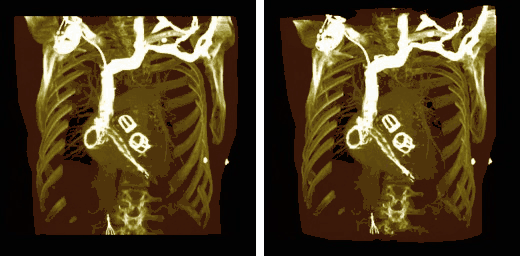

Volume Rendering

- Volume rendering can be applied to the voxel data in the successive rotation manner described for MIPs above, as illustrated in Figure 5.25. A superior display to that of MIPs is clearly evident.

- Note that the volume rendering can be contrast enhanced so as to threshold, for instance, through the voxel values to eliminate lower attenuation surfaces, as illustrated in Figure 5.26.

- Note also that the colour look-up table (CLUT) can be varied to highlight features of particular interest, as shown in the set of images in Figure 5.27. A vast range of CLUTs is available with the four shown being used here solely for illustrative purposes.